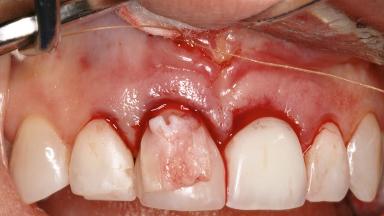

Late Presentation of Peri-Implant Mucositis Requiring Soft-Tissue Augmentation and Esthetic Crown Lengthening at Implant Site 11